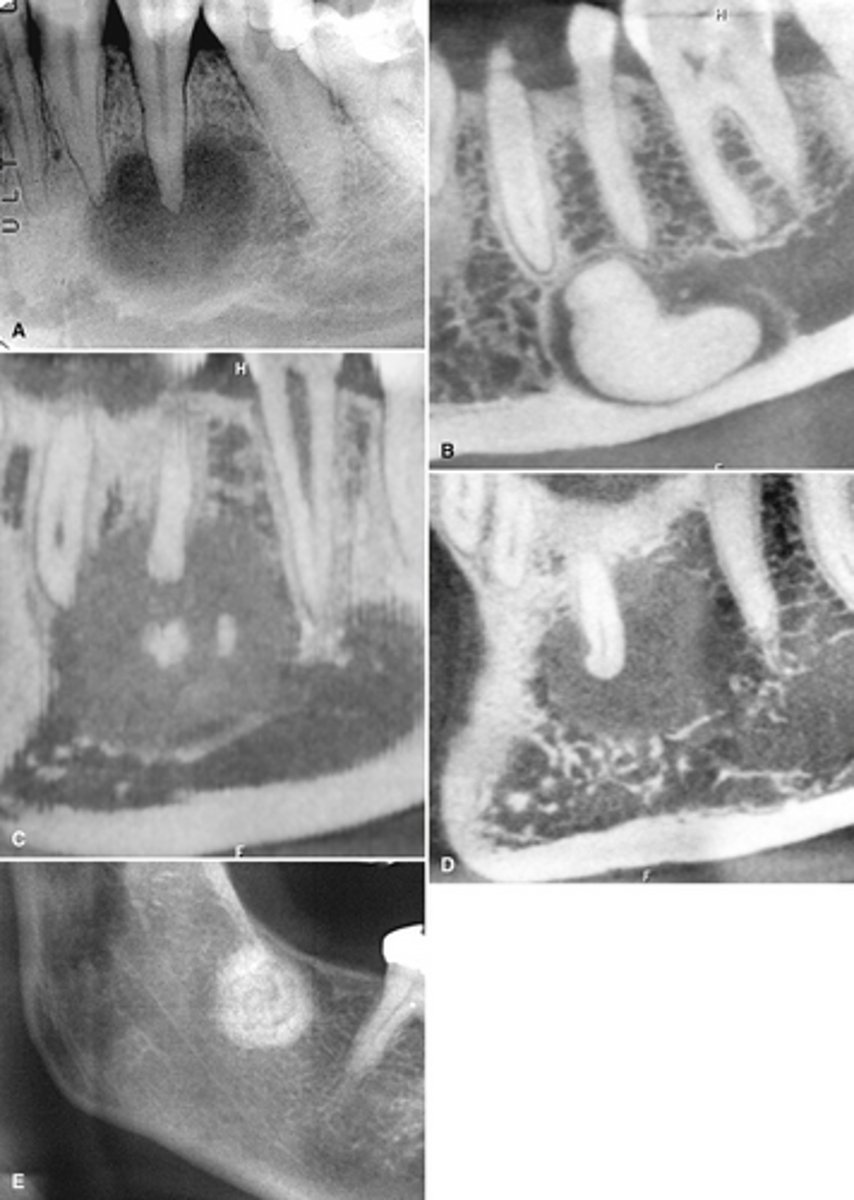

Patient has DJD.

The top images show the subchondral/ Ely cyst, a pseudocyst of connective tissue, granular tissue and osteoid, the bottom images show the same patients left side with broad erosion, a lack of cortication, loss of joint space.

What is the diagnosis of the patient based off these radiographs and what are the features? (Top images = patients right condyle) (bottom images= same patients left condyle)